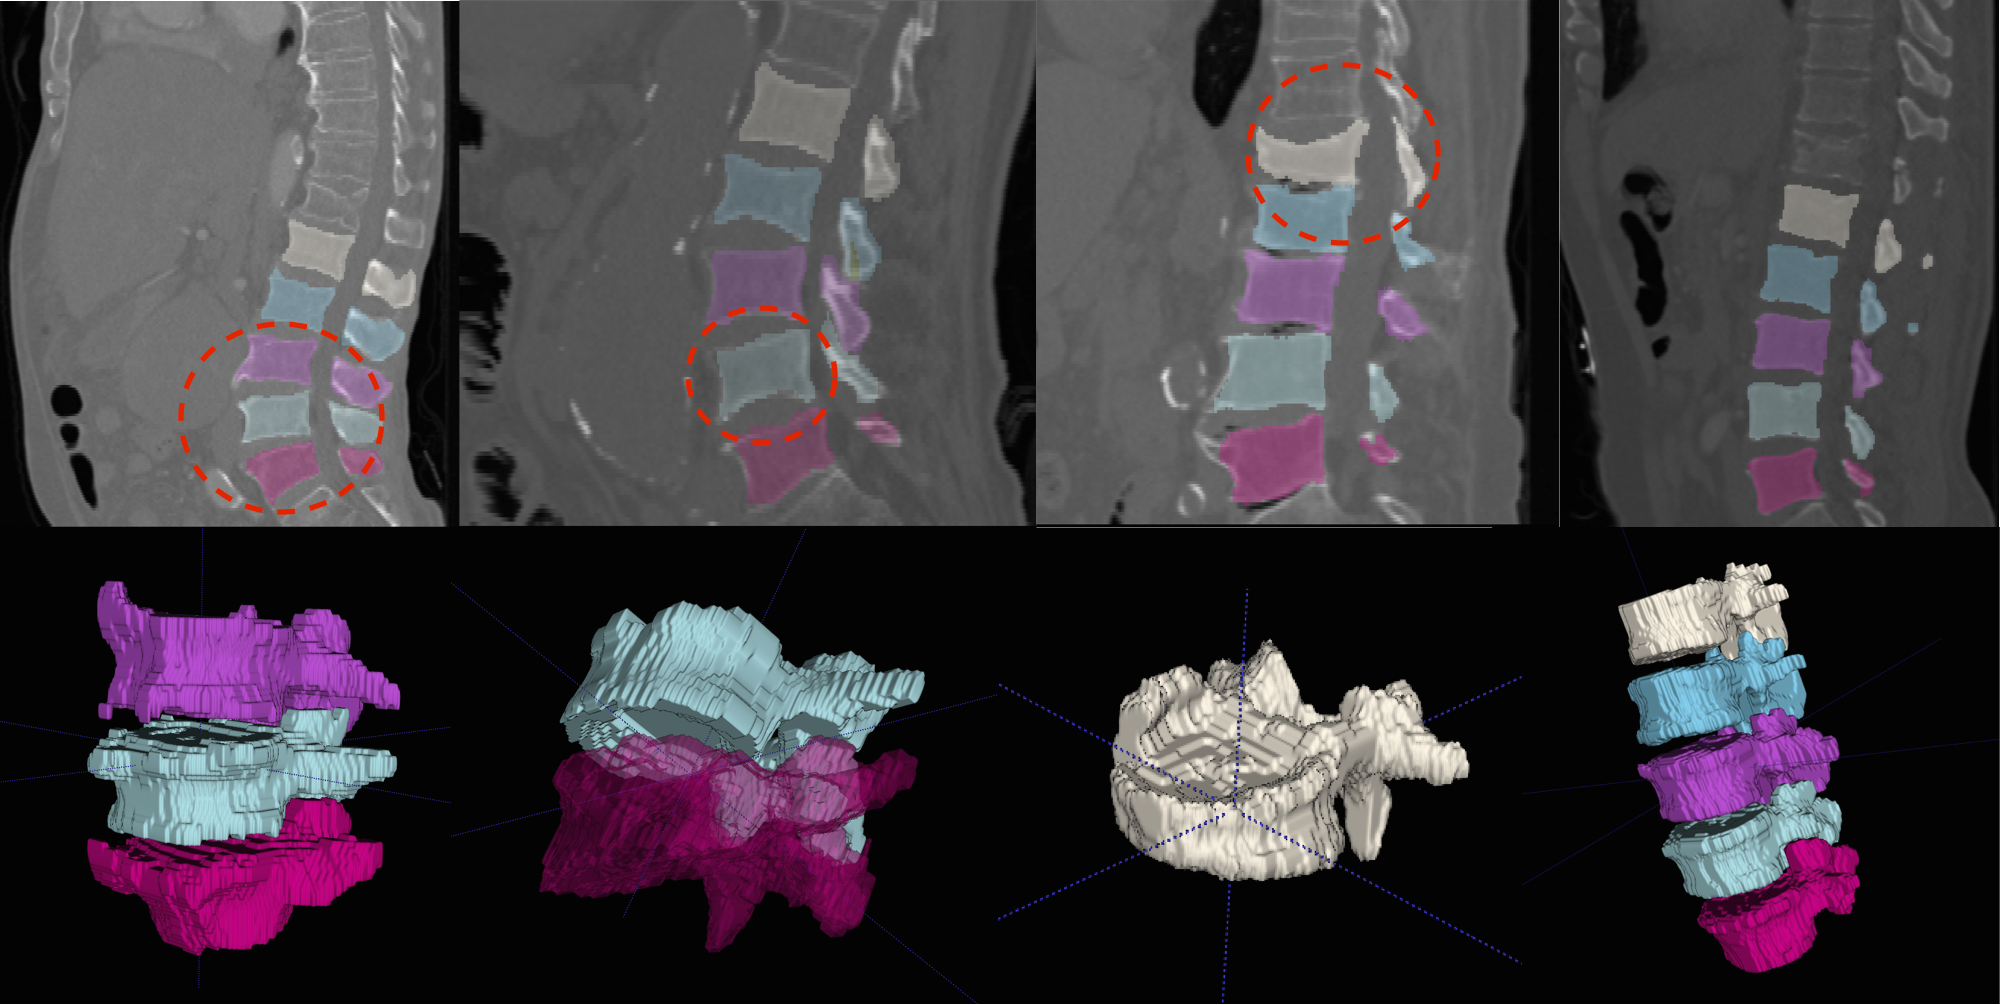

In general, both the stages in our pipeline work remarkably well as per the quantitative results in tables 1 and 2. We obtain a near perfect localisation of 1.0 for almost every case, and a mean Dice score of 92%. In addition to this, the prime motivation of our approach is to successfully segment the deformed spines where the model-based approaches fail. This can be observed visually in figure 4. Four test cases as shown highlighting the highly deformed spine and vertebrae. Observe that our algorithm successfully segments these cases in spite of the severe deformations.

Refer to caption

Figure 4: Multi-class Segmentation: (Row 1) Four sagittal slices where the deformed vertebrae are highlighted, with (Row 2) the 3D rendering of the deformed vertebrae for better visualisation. More visualisations on deformed vertebrae will be made available as supplementary material.

We present more results of multi-class segmentation on the test set of xVertSeg (figure 5) in addition to the results in figure 4, thereby emphasising the robustness of our approach. We also present a few aberrant segmentations analysing which could further improve our approach.